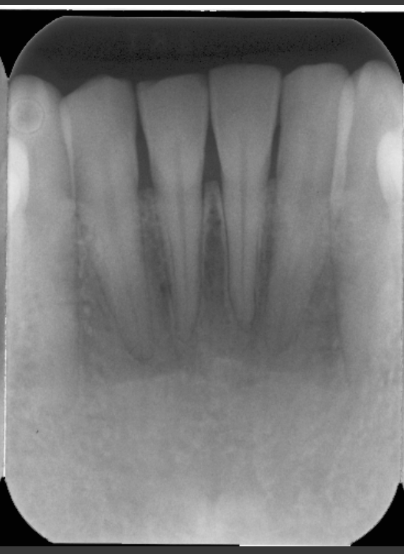

What is foreshortening the roots?

It means we have an excessive angulation which shortens the roots and elongates the crown.

Foreshortening= excessive vertical angulation

Elongation= insufficient vertical angulation

What leads to elongation in a radiograph?

When there is insufficient angulation when taking a maxillary or mandibular photo.